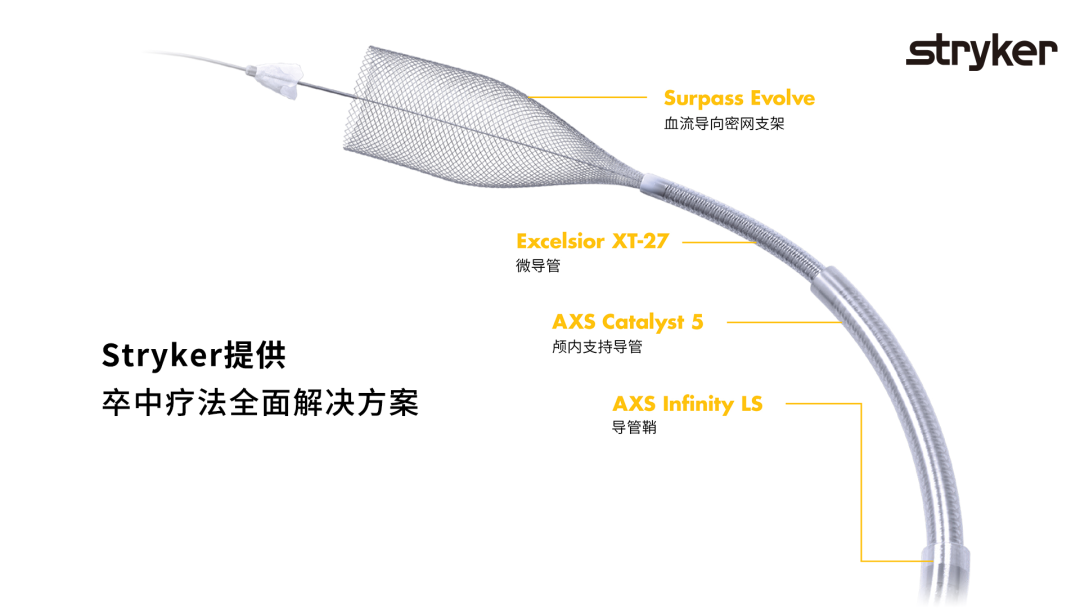

6F 导管长鞘

5F 115cm 中间管

XT-27 微导管

微导丝

Surpass Evolve 5*30mm 血流导向密网支架

微导管到位后释放支架头端。

头端完全打开,锚定。

完全覆盖动脉瘤颈后拟过弯。

支架完全释放。

造影明确打开贴壁满意。

大动脉瘤的微创介入栓塞治疗存在需要支架辅助,瘤颈处理困难、复发率高、费用高等难点;血流导向密网支架置入是较优选择,操作相对简单,不用填塞弹簧圈,完整覆盖瘤颈,远期明显降低再复发概率。本病例为右侧颈内动脉C7段累及脉络膜前动脉的大动脉瘤,该部位解剖结构复杂,周围血管分支多,在操作过程中要避免损伤正常血管,否则会引发严重脑缺血事件;其次,动脉瘤与脉络膜前动脉关系密切,既要处理好动脉瘤,又要保证脉络膜前动脉的血供不受影响,这对手术操作精度要求较高;再者,瘤颈的处理较为棘手,瘤颈较宽,传统弹簧圈栓塞难以达到理想效果,且容易复发。血流导向密网支架置入可解决这些问题,术前需借助3D-DSA,全面评估动脉瘤大小、形态、瘤颈宽度、与周围血管关系,制定精准手术方案。操作时,微导管的到位是关键一步,要在路径图引导下,小心、轻柔操作,避免刺激血管引发痉挛或动脉瘤破裂。释放支架过程中,要注意关注支架位置和贴壁情况。释放后要通过多角度造影,确认支架完全覆盖瘤颈,且支架内血流通畅,分支血管未受影响。同时,术后要密切观察患者神经功能变化,预防血栓形成、血管痉挛等并发症,及时给予抗血小板、解痉等药物治疗。

Surpass Evolve血流导向密网支架是专为颅内动脉瘤介入治疗设计的血流导向装置,采用钴铬合金编织网,金属覆盖率可达30-35%;头端易打开,具备优异的贴壁性,通过性优越,适合迂曲血管路径;多规格可选;适用于复杂型(大型、巨大型、梭形或宽颈)颅内动脉瘤。